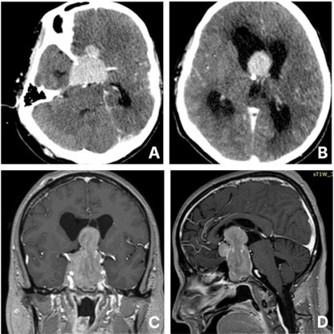

A 57-year-old male with no significant past medical history presented to the emergency department with a sudden onset of severe headache, vomiting, and progressive loss of consciousness. He was intubated for airway protection on arrival due to collapse. Initial CT imaging revealed a giant sellar lesion extending into the third ventricle, causing obstructive hydrocephalus (Figure 1). An emergent External Ventricular Drainage (EVD) was placed, and the patient was admitted to the Intensive Care Unit (ICU), where he was started on intravenous dexamethasone. Further systemic examination revealed an absence of body hair on the trunk and limbs, while facial and pubic hair remained intact. He exhibited no gynecomastia or galactorrhoea, and testicular volume was within normal limits. The family reported long-standing hair loss since adolescence, but had fathered four children by the age of 30. Laboratory investigations showed low levels of Follicle-Stimulating Hormone (FSH), Luteinizing Hormone (LH), testosterone, Growth Hormone (GH), and Free Thyroxine (FT4), with a normal Thyroid Stimulating Hormone (TSH) level and low Prolactin (PRL). He was started on levothyroxine for presumed central hypothyroidism.

MRI confirmed the presence of a giant sellar lesion extending into the suprasellar region and 3rd ventricle to the foramen of Monro (Figure 1). The lesion exhibited enhancement and diffusion restriction on Susceptibility-Weighted Imaging (SWI), with invasion of the bilateral cavernous sinuses and encasement of the internal carotid arteries. Also, the optic chiasm was compressed. In reduced sedation attempts, the patient was decerebrating.

Figure 1: A and B show axial cuts of the initial CT head post contrast. C and D illustrate the lesion in the pre-op MRI in sagittal and coronal views.